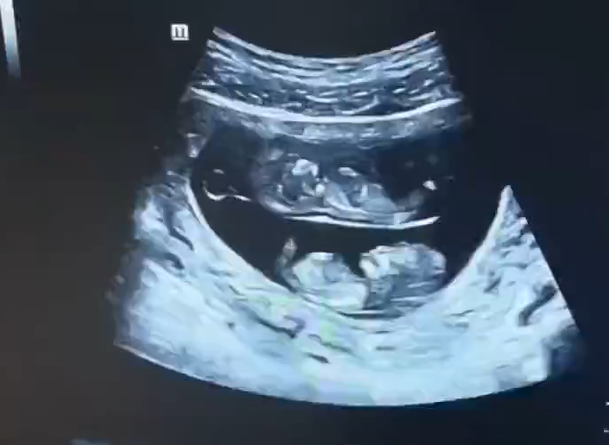

孕妇做B超拍到上下铺宝宝 网友:真·睡在我上铺的兄弟

9月3日,河南的一位孕妇妈妈晒出了一对双胞胎宝宝的B超照...